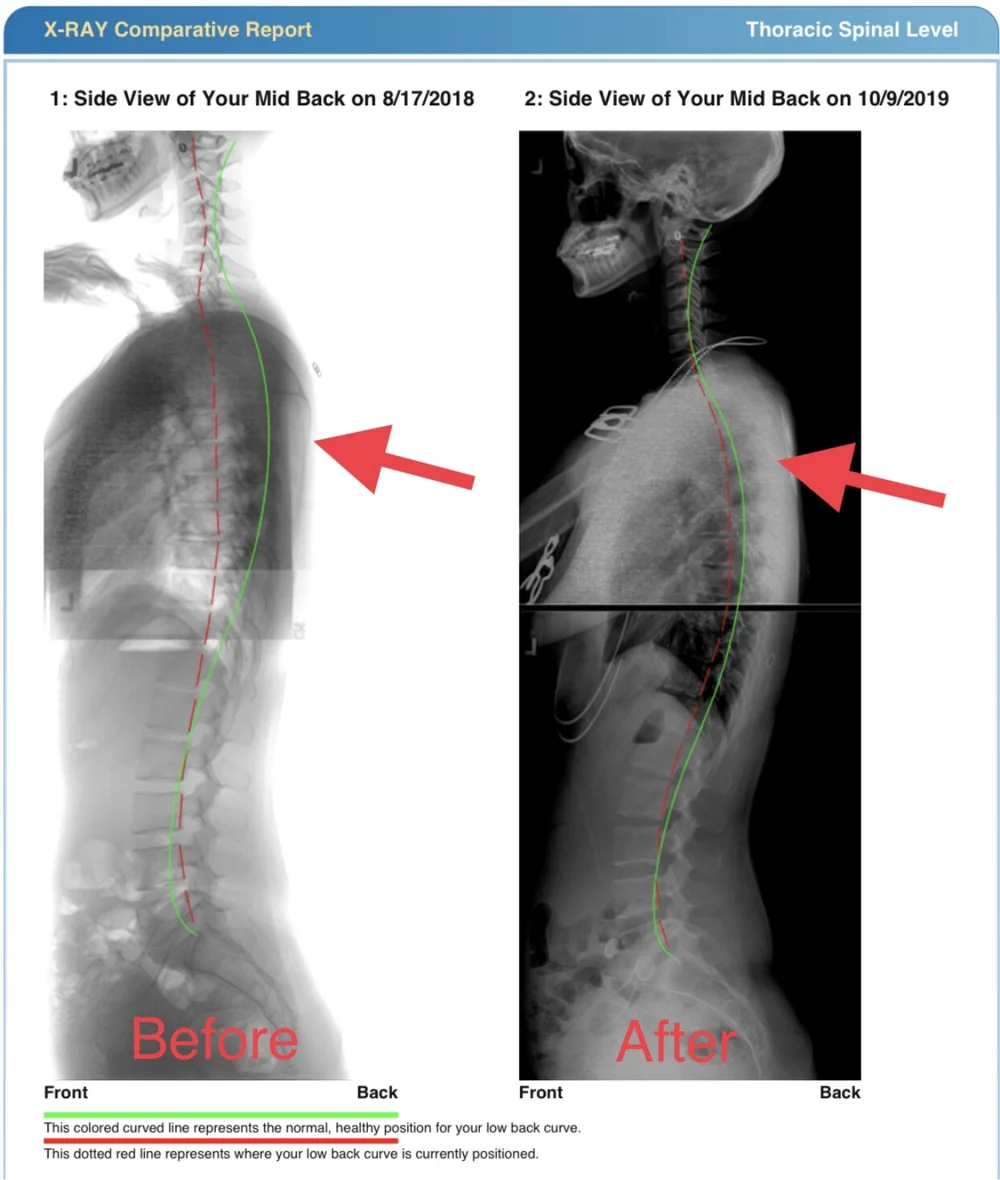

Postural Correction Using Denneroll In Smithtown And Selden Ny

Thoracic Denneroll Chiropractic Biophysics

Denneroll Thoracic Orthotic Traction Unit Chiropractic Biophysics

Improving Your Back Posture With Chiropractic Biophysics Mirror Image Methods Improves Chronic Low Back Pain By 73 Chiropractic Biophysics Nonprofit